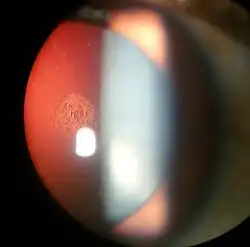

Magnified view of a cataract seen on examination with a slit lamp